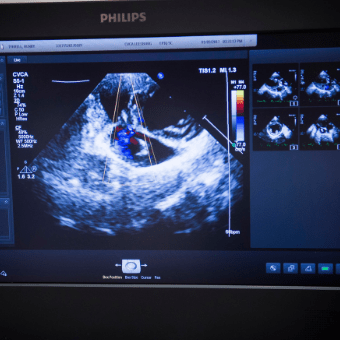

Echocardiogram

CVCA – Cardiac Care for Pets performs thousands of “echos” each year. You will be with your pet while the Cardiologist evaluates their heart!